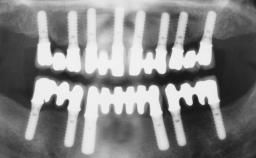

Immediate Loading of Six Implants in the Maxilla and Final Restoration with a Full-Arch CAD/CAM Zirconia FDP

A 63-year-old male patient was referred for a consultation and treatment of partial edentulism in the maxilla. The patient presented with residual anterior teeth and declined a partial removable prosthesis. He reported that the maxillary posterior teeth had been extracted due to mobility and periodontal disease two months before the consultation. The patient’s chief complaint was that his residual maxillary teeth were mobile and that he was unable to chew. The patient’s desire was a stable and comfortable fixed maxillary rehabilitation. The patient was a light smoker (fewer than 10 cigarettes/ day), and his medical history was without significant findings. He was not on any regular medication at the time of consultation. The extraoral examination revealed a normal physiognomy with a correct distribution of the facial thirds. The patient presented a low lip line, and the transition line between teeth and soft tissues was not exposed during a forced smile.

# of Implants 6

Type of Implants One-Piece

Modality 6+ implants with immediate loading